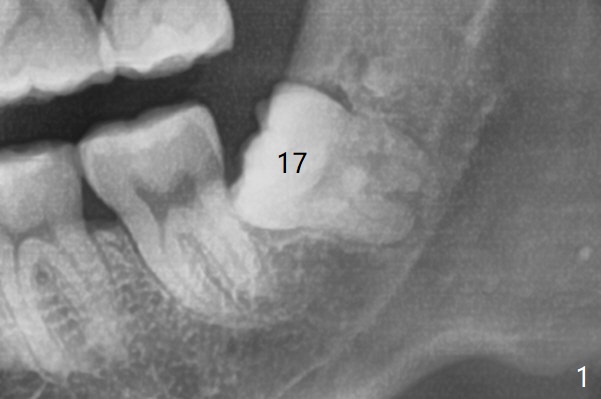

Midbuccal Incision     Last     Next

Xin Wei, DDS, PhD, MS 1st edition 06/24/2020, last revision 06/25/2020